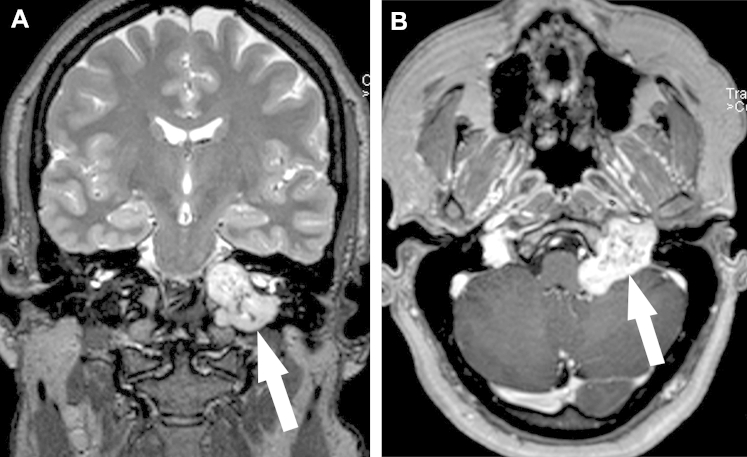

Subsequent MRI examination showed a 3.8 × 3.5 × 3.5 cm3 dumbbell-shaped lesion with a “salt & pepper” appearance on coronal T2W-imaging in the left JF (Fig. 2A), with involvement of the left internal auditory canal, hypoglossal canal, clivus, and cerebellopontine angle. This lesion demonstrated avid enhancement on postcontrast imaging (Fig. 2B). There was associated mass effect on the left medulla and anterior inferior left cerebellum, and obscuration of the left-sided cranial nerves VII-XII. The distal left cervical internal carotid artery just proximal to the horizontal petrous segment was asymmetrically small in caliber, and the left internal jugular vein was not seen.

Fig. 2.

MRI examination showing (A) a dumbbell-shaped lesion with demonstration of “salt & pepper” appearance on coronal T2W imaging (arrow), and (B) an avidly contrast-enhancing mass in the JF with prominent central flow voids corresponding to a “pepper”-like appearance on axial-T1W imaging (arrow).